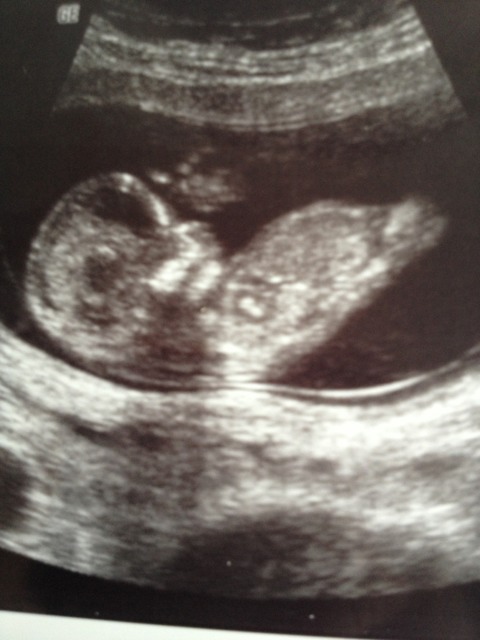

U/S tech didn't really know about the nub shot so she did a potty shot instead. It seems very very much like it is a boy from the pic. Are potty shots accurate that early? I swayed for a girl and already have two lovely boys. Tech was convinced it was a boy too. Attachment 10387Attachment 10388